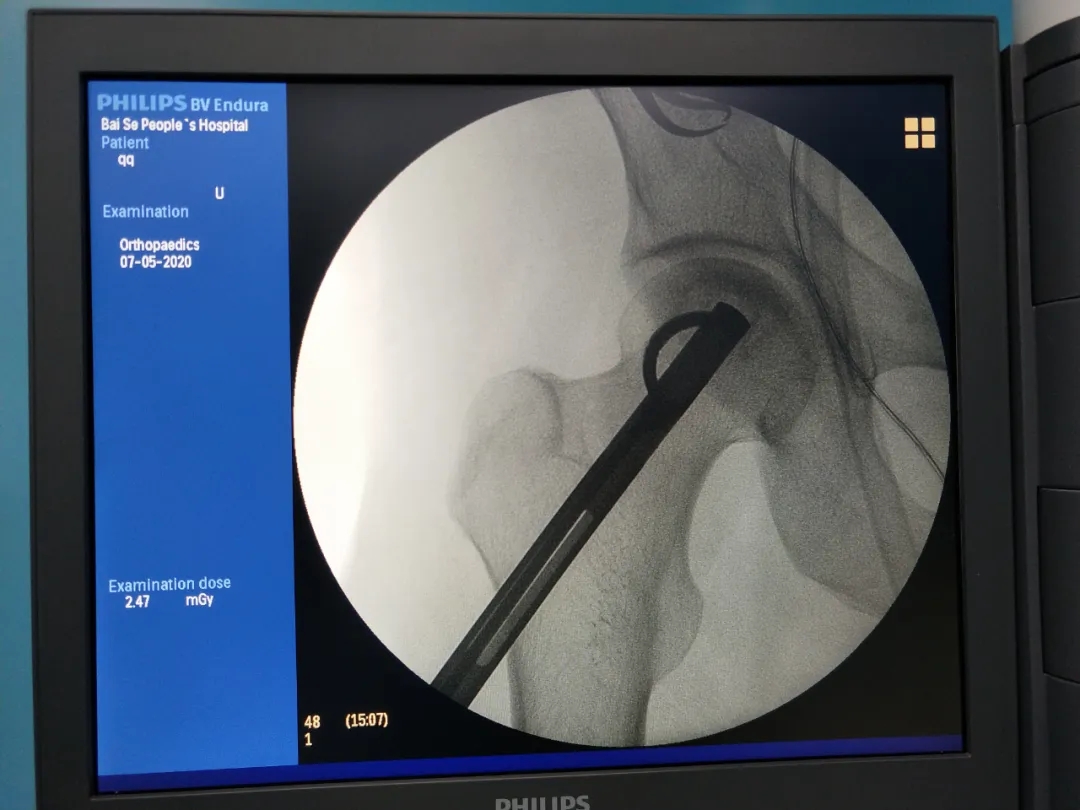

开展天玑?骨科手术机械人辅助下早期股骨头坏死病灶扫除植骨术。。。。。。天玑?骨科手术机械人系统收罗图像后,,,,,,设计导针偏向和位置,,,,,,按设计一次性精准的将导针置入妄想位置,,,,,,将坏死区刮除彻底,,,,,,然后用人工骨和自体骨充分填充坏死区,,,,,,增进局部愈合,,,,,,延缓股骨头坏死希望,,,,,,尽可能阻止髋枢纽置换,,,,,,也真正体现了“精准微创”的治疗理念。。。。。。

机械人术前设计

术中操作